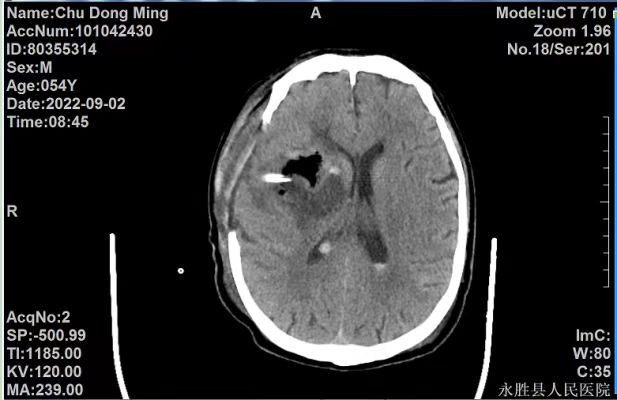

病例一:患者,男性,54岁,因“突发言语不清,意识模糊伴左侧肢体活动障碍5小时余”入院。入院后CT检查示:右侧基底节区急性大量脑出血,出血破入脑室系统,右侧侧脑室受压、中线结构向左移位。入院后诊断为:1.右侧基底节脑出血并破入脑室;2.脑疝形成;3.高血压3级,很高危组。患者病情危重,随时可能出现呼吸心跳骤停死亡,葛主任得知情况后迅速赶到医院,指导科室立即为患者实施开颅血肿清除术,手术顺利。目前患者正在做康复治疗。

术前

术后